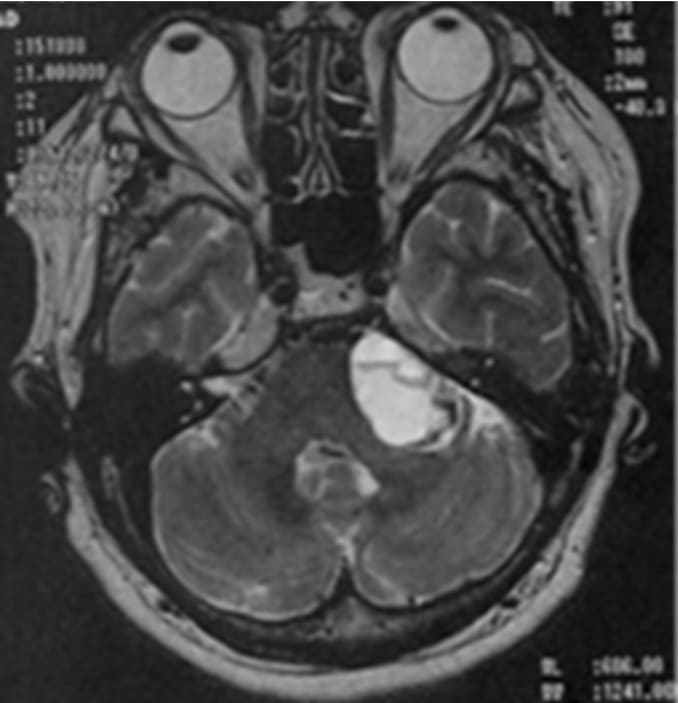

巨大のう胞性聴神経腫瘍症例に対する治療計画

聴神経腫瘍1400症例中、外科手術を要したのは実に6名のみ(いまのところ術中に強い癒着を呈していたという報告はありません)。一方で、大方の患者さんは6か月後に一過性膨大を伴います。これは高線量一括照射に伴う腫瘍内部の栄養血管が強い炎症反応(血管炎)を呈することが主因であり、腫瘍が成長し続ける腫瘍増大とは異なります。腫瘍中心に造影欠失像(Loss of central enhancement/LCE)として描出されることが特徴となっています。

他の神経鞘腫には同様に認められますが、髄膜腫など他の脳腫瘍にはまず認められない特徴的な所見となっています。その際に、初動時のふらつきを訴える患者さんもおりますが、難聴や顔面麻痺などは通常起こりません。この炎症反応はさらに6か月後には収まり、治療時とほぼ同サイズへと戻ります。その後1-2年して、全体の75%ほどが縮小傾向に入り、10年経てもさらに縮小し続けるのが特徴となっています。

巨大のう胞性聴神経腫瘍症例ガンマナイフ治療後経過

顔面麻痺・聴力障害もなし